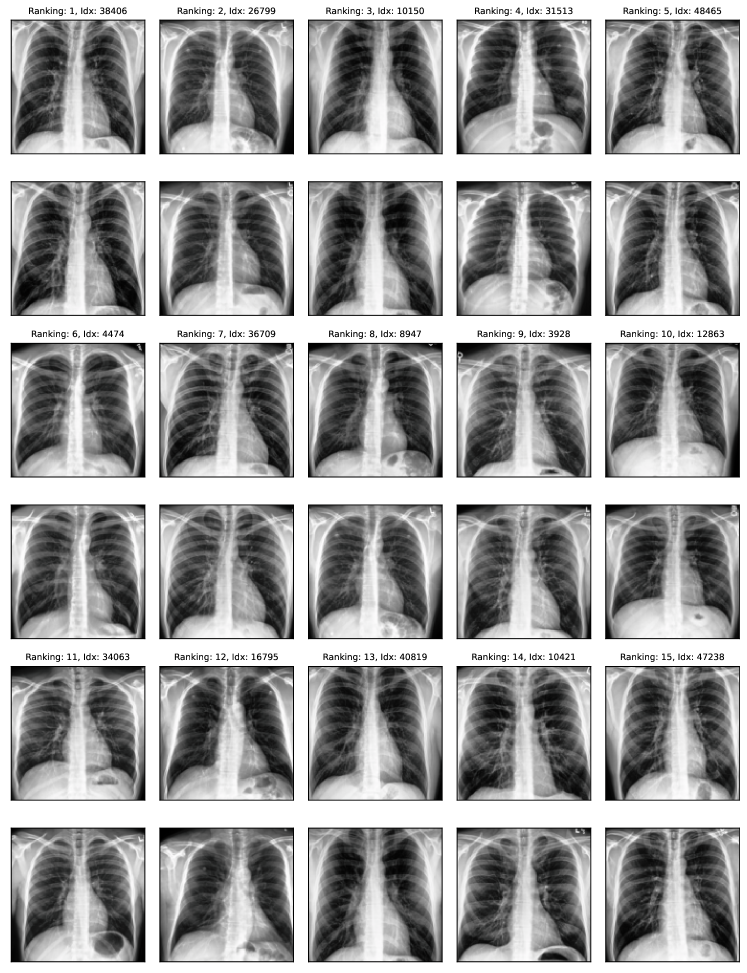

Natural experiment setup. To further validate the proposed approach, we evaluate it on data quality issues naturally found in benchmark datasets. To this end, we devise two different experiments. In the first experiment, we measure how well the ranking matches available metadata, e.g. if two images show the same person or if the label was obtained using gold-standard tools in medical diagnosis. This experiment is, however, specific to each dataset depending on the applicability of the available metadata. Therefore, in a second experiment, we use SelfClean to propose a ranking for some datasets and gather partial human annotations for validation. We collect annotations from medical experts for the medical datasets and rely on crowd workers for general image datasets. We then evaluate the proposed ranking using human annotations as described in appendix I.

Comparison with human annotators. We evaluate SelfClean rankings based on human annotations across two medical and two common vision benchmarks as described in appendix I. The evaluation reveals that images ranked by SelfClean as the most likely to contain data quality issues are also identified by human experts as problematic significantly more often than random images. As shown in table 8, we find 95% significant differences in nine of twelve evaluations for comparing the lowest 50 ranked images to a random selection and six of ten evaluations for comparing images ranked 1-25 to images ranked 26-50. Two cases in the second comparison are excluded because too many positive samples give undefined metrics. Results indicate that the proposed ranking, to a large degree, coincides with human understanding of these three noise types. Therefore using SelfClean can increase efficiency when analyzing and fixing data quality issues.